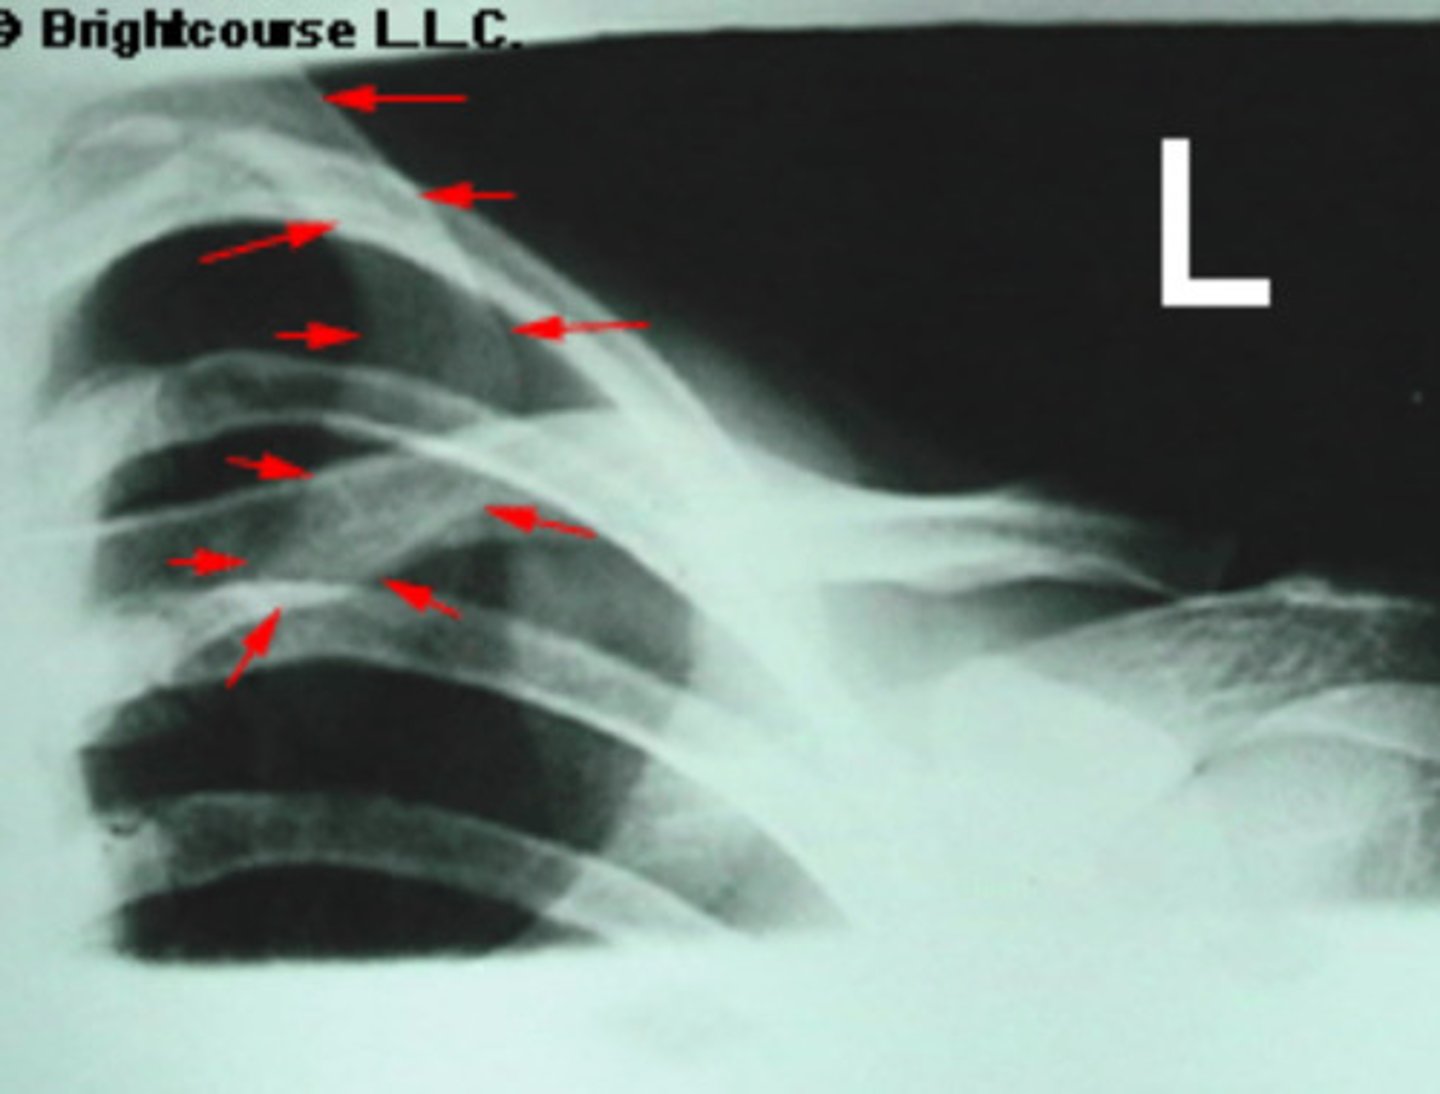

Lesser tubercle

What is being pointed out by the arrows in the image?